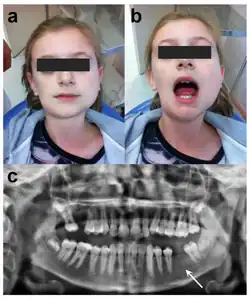

Diagnosis of oral tori are usually done during a dental examination by a dentist or a specialist in dentistry. The bony growth may be recognized during dental procedures, cleanings, or just regular check-ups.

During a routine exam, the dentist may be able to diagnosis this condition through a visual examination by inspecting the mouth for any irregularities such as bony growths. The dentist during this visual exam will focus on the palate, lingual side of the lower jaw, and the outer areas of the upper and lower jaws. Once visual examination indicates an oral torus, the dentist will then feel for palpation in the suspect area in order to further examine the size, shape, and firmness of the oral tori. Though imaging is not necessary to diagnose oral tori, the dentist may decide to do imaging to rule out cysts or tumors (which may cause similar symptoms or have similar factors) by taking an x-ray (for a 2D view) or CT scan (for a 3D view) of the mouth to get a better view of the exact size and location of the growth.[13]